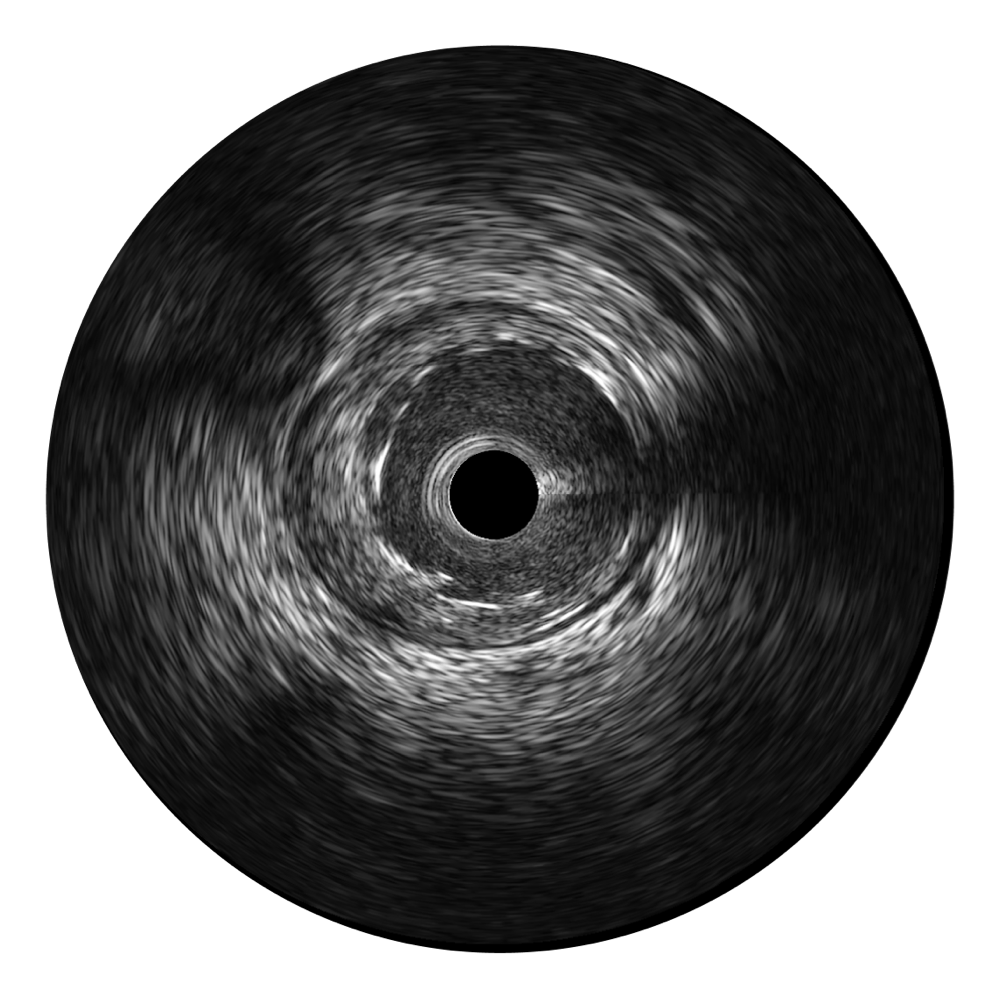

诸侯快讯官网宽频IVUS图像

传统IVUS图像

对比传统IVUS导管成像,诸侯快讯官网宽频IVUS图像的近场支架梁显影更细腻,远场中膜外血管仍清晰可辨,兼顾远中近,兼顾分辨力与穿透深度